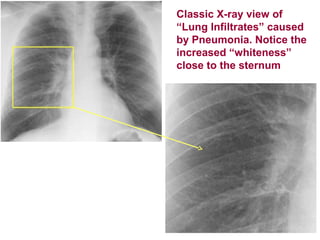

Classic X-ray view of

“Lung Infiltrates” caused

by Pneumonia. Notice the

increased “whiteness”

close to the sternum

Classic X-ray viewof “Lung Infiltrates” caused by Pneumonia. Notice the increased “whiteness” close to the sternum